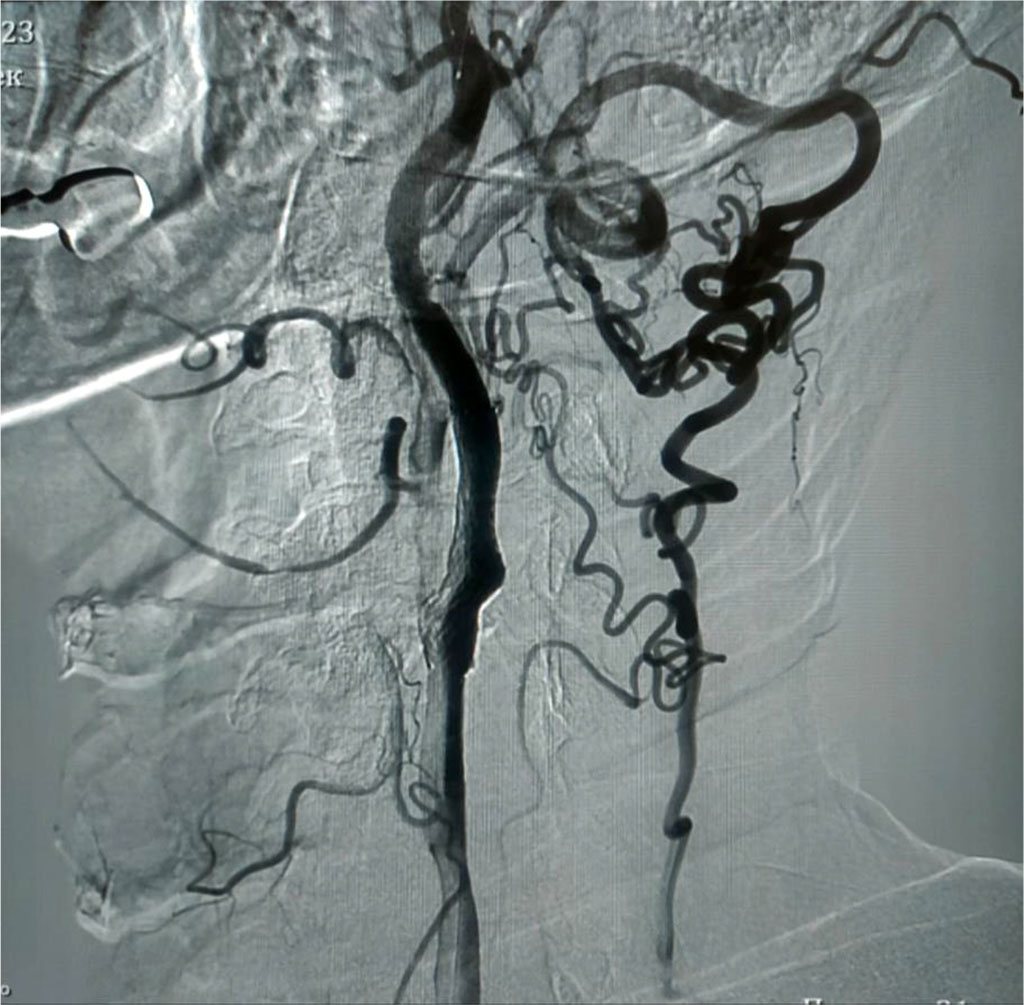

Carotid angiography shows that the blood supply to the brain is provided by a single internal carotid artery on the left and a potent collateral network on the same side. Intracranially, both hemispheres are supplied with blood from one side. Fig. 1.

Fig. 1. Carotid angiography. Stenosis of the internal carotid artery on the left (91%), visible collaterals

Diagnosis: Atherosclerosis of the brachiocephalic arteries. Occlusion of the internal carotid artery on the right. Subocclusion of the internal carotid artery on the left (91%). Chronic cerebrovascular insufficiency of the 4th degree (according to A.V. Pokrovsky) [13]. Condition after three ischemic strokes.